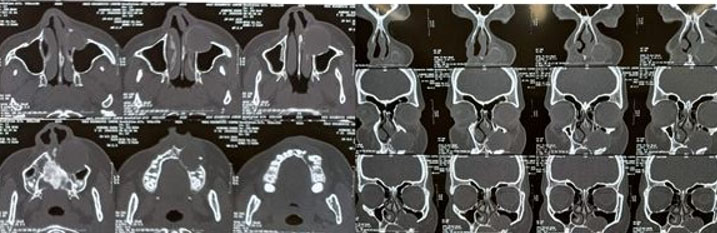

The patient was in the third trimester; therefore, surgery was planned for a later date. Pre-operative CT scan revealed a well-defined unilocular expansile non-homogenous hypodense area with a well-defined corticated border extending from the periapical region of 22–26 (anteroposteriorly) and from the alveolar bone to the maxillary sinus (superoinferiorly). Internal architecture showed the presence of a well-defined tooth-like structure along the inferior aspect, most likely to be a horizontally impacted maxillary canine. Medial displacement of the lateral nasal wall was noted on the left side. Superior displacement of floor of maxillary sinus was noted on left side, causing reduction in sinus volume of left maxillary sinus. Displacement of buccal cortical plate was noted in relation to the lesion suggestive of cortical expansion. Some areas of discontinuity were noted in the buccal cortical plate suggestive of perforation. There was no evidence of external root resorption with maxillary left canine and premolars. Computed tomography examination gave a clearer picture of the extent of the lesion for appropriate surgical planning (Figure 3).

Figure 3: CT scan. Well-defined unilocular expansile non-homogenous radiolucency with well-defined corticated border noted in maxillary anterior region on the left side associated with an impacted tooth with involvement of lateral nasal wall, anterior wall and floor of maxillary sinus and buccal cortical plate.